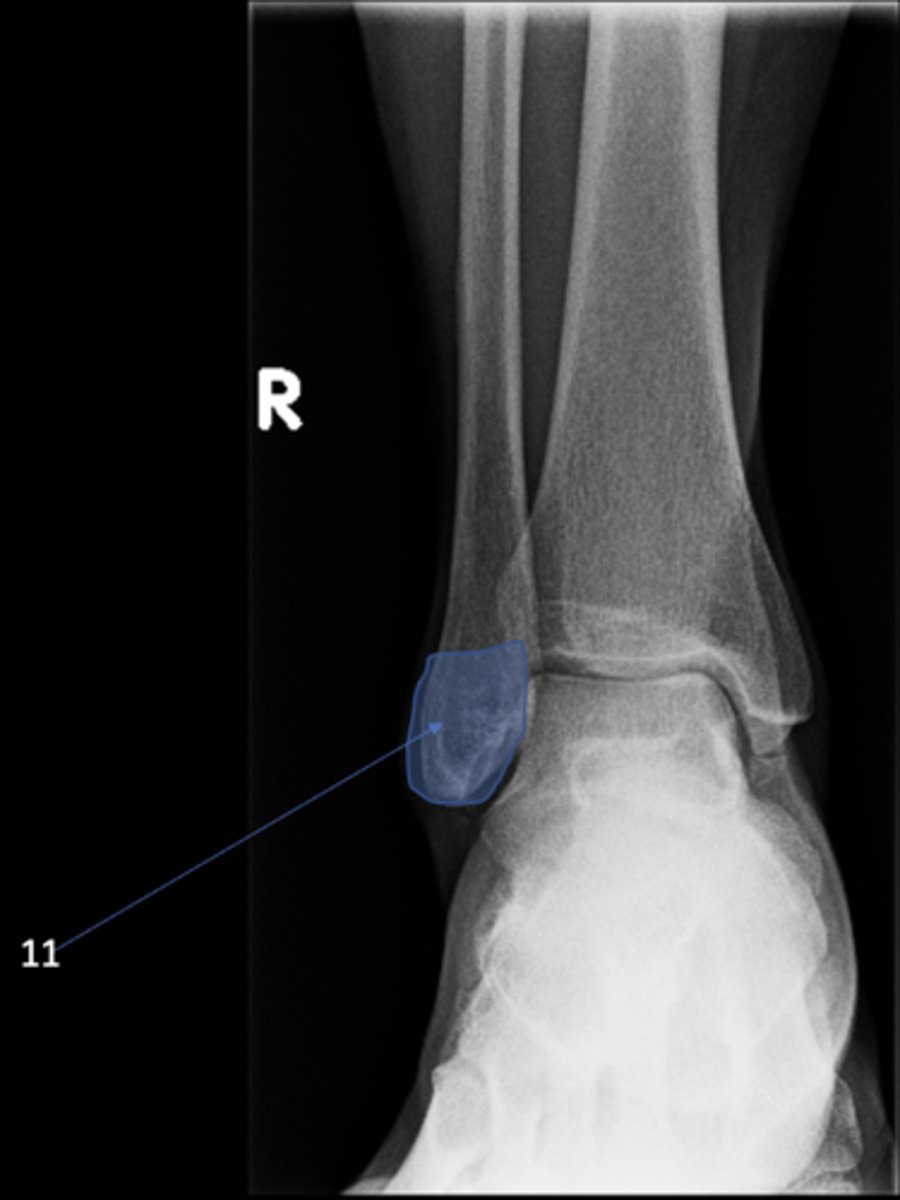

New cards

Right AP ankle

View?

77

Lateral malleolus

ID 11